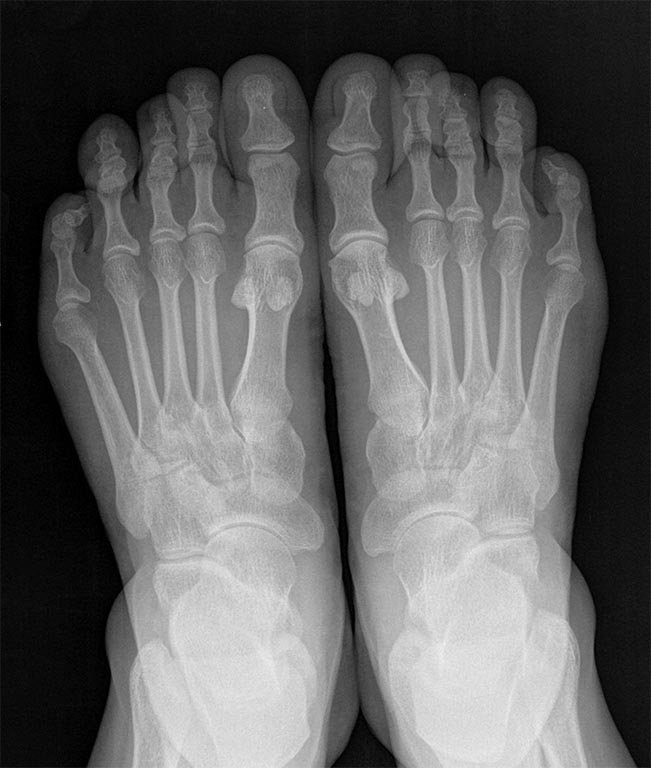

Пациентка 40 лет, жалобы на длинные 4 пальцы обеих стоп, трудности с

подбором обуви, чисто косметический дефект, болей натоптышей нет. За

счет чего лучше сделать укорочение, плюсневой кости и основной фаланги

(если фаланга чем фиксировать).